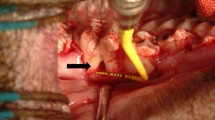

A full thickness chondral defect measuring 6 mm in diameter was generated in a load-bearing area of the host animal’s medial femoral condyle in each posterior miniature pig limb using a biopsy punch, followed by removal of the calcified cartilage layer (Fig. 1). The full-thickness damaged cartilage was covered with the biomaterial scaffold alone in one limb and scaffold loaded with DPSCs in the other posterior limb (described above). The scaffold was stabilized with 6–0 vicryl sutures.